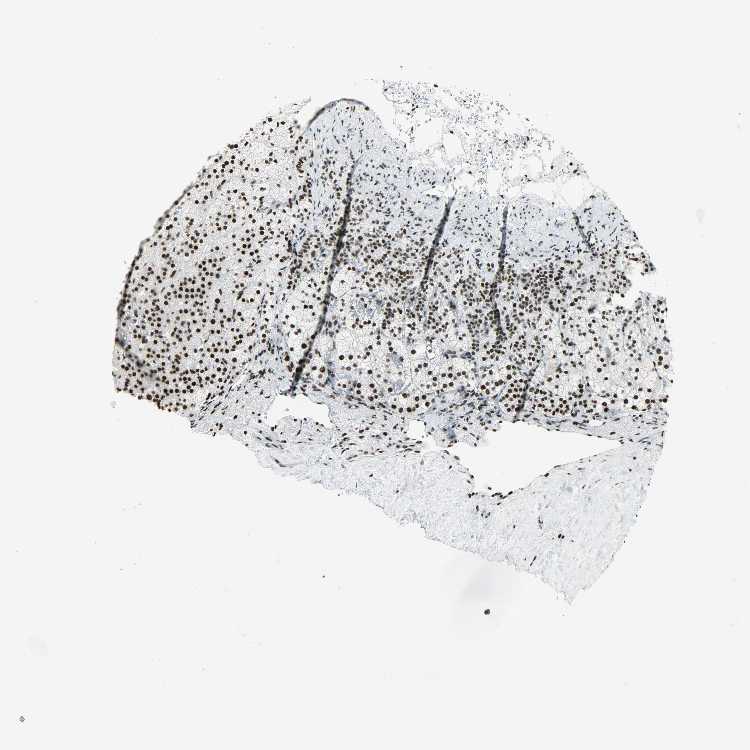

ADRENAL GLAND - Antibody stainingi

Antibody staining in the annotated cell types in the current human tissue is reported as not detected, low, medium, or high, based on conventional immunohistochemistry profiling in selected tissues. This score is based on the combination of the staining intensity and fraction of stained cells.

Each image is clickable and will lead to virtual microscopy that enables deeper exploration of all samples and also displays staining intensity scores, fraction scores and subcellular localization as well as patient and tissue information for each sample.

Antibody HPA046440Antibody CAB004652

Glandular cells MediumHigh